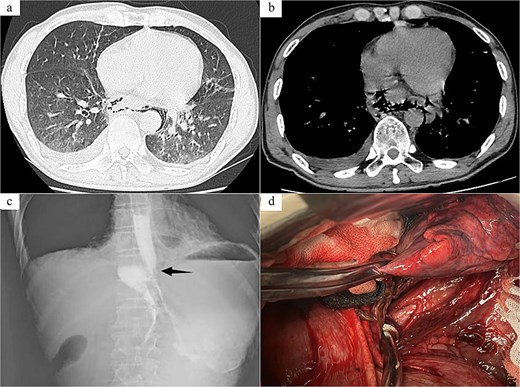

Case 2: The patient, a 54-year-old male, was admitted to Emergency Department due to “nausea, hematemesis accompanied by abdominal and thoracic pain for half a day.” On admission, imaging studies including chest and abdomen CT revealed periesophageal air around the lower segment of the esophagus, mediastinal emphysema, and multiple air in abdominal cavity, bilateral pleural effusion (Fig. 2a and b). Esophagus echoendoscopy showed contrast agent leakage at the distal aboral esophageal segment (Fig. 2c). Electrocardiogram showed no abnormalities. Blood routine test showed that white cell count 12.49 × 109/L, neutrophil count 11.19 × 109/L, neutrophil percentage 89.6%. In summary, the diagnosis was SRE. In emergent surgery under general anesthesia, laparoscopic repair of esophageal tear was performed. Intraoperative exploration revealed a long tear of about 3.0 cm in the posterior wall of the lower esophagus near the cardia (Fig. 2d), and the esophageal wall and mediastinal pleura around the tear were observed to have grayish-brown-like changes, and a long interspace about 5.0 cm was seen under the post-cardiac abdominal membrane, which was filled with gastric contents that had overflowed. The same surgical approach as Case 1 was employed. The surgical method was the same as Case 1. And a T-shaped tube was placed in the subphrenic space behind the cardia for drainage and drainage tubes were placed in the posterior mediastinum and the chest cavity, respectively. Postoperative anti-infection, gastrointestinal protection, and enteral nutrition therapy were given. Half a month after the operation, the patient was examined with upper digestive tract radiography and chest CT, which showed that there was no leakage or stenosis the anastomotic site of the esophagus. The patient was allowed to resume eating after fasting for 16 days and was discharged after recovery.

Radiology images and emergency surgery photos of spontaneous esophageal rupture (Case 2). (a and b) Chest and abdomen computed tomography revealed periesophageal air around the lower segment of the esophagus, mediastinal emphysema, multiple air in abdominal cavity, bilateral pleural effusion. (c) Esophagus echoendoscopy showed contrast agent leakage at the distal aboral esophageal segment (black arrow). (d) Emergency surgery revealed a long tear of about 3.0 cm in the posterior wall of the lower esophagus near the cardia.